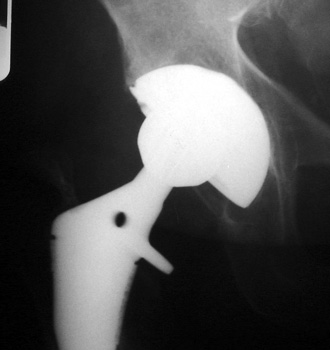

Polyethylene cup dislocation. AP radiograph demonstrates eccentric positioning of femoral head in cup with subtle curvilinear density inferiorly corresponding to dislocated polyethylene liner. Arthrographic spot film demonstrates contrast outlining the polyethylene liner. Model of total hip replacement components positioned with polyethylene liner dislocated.